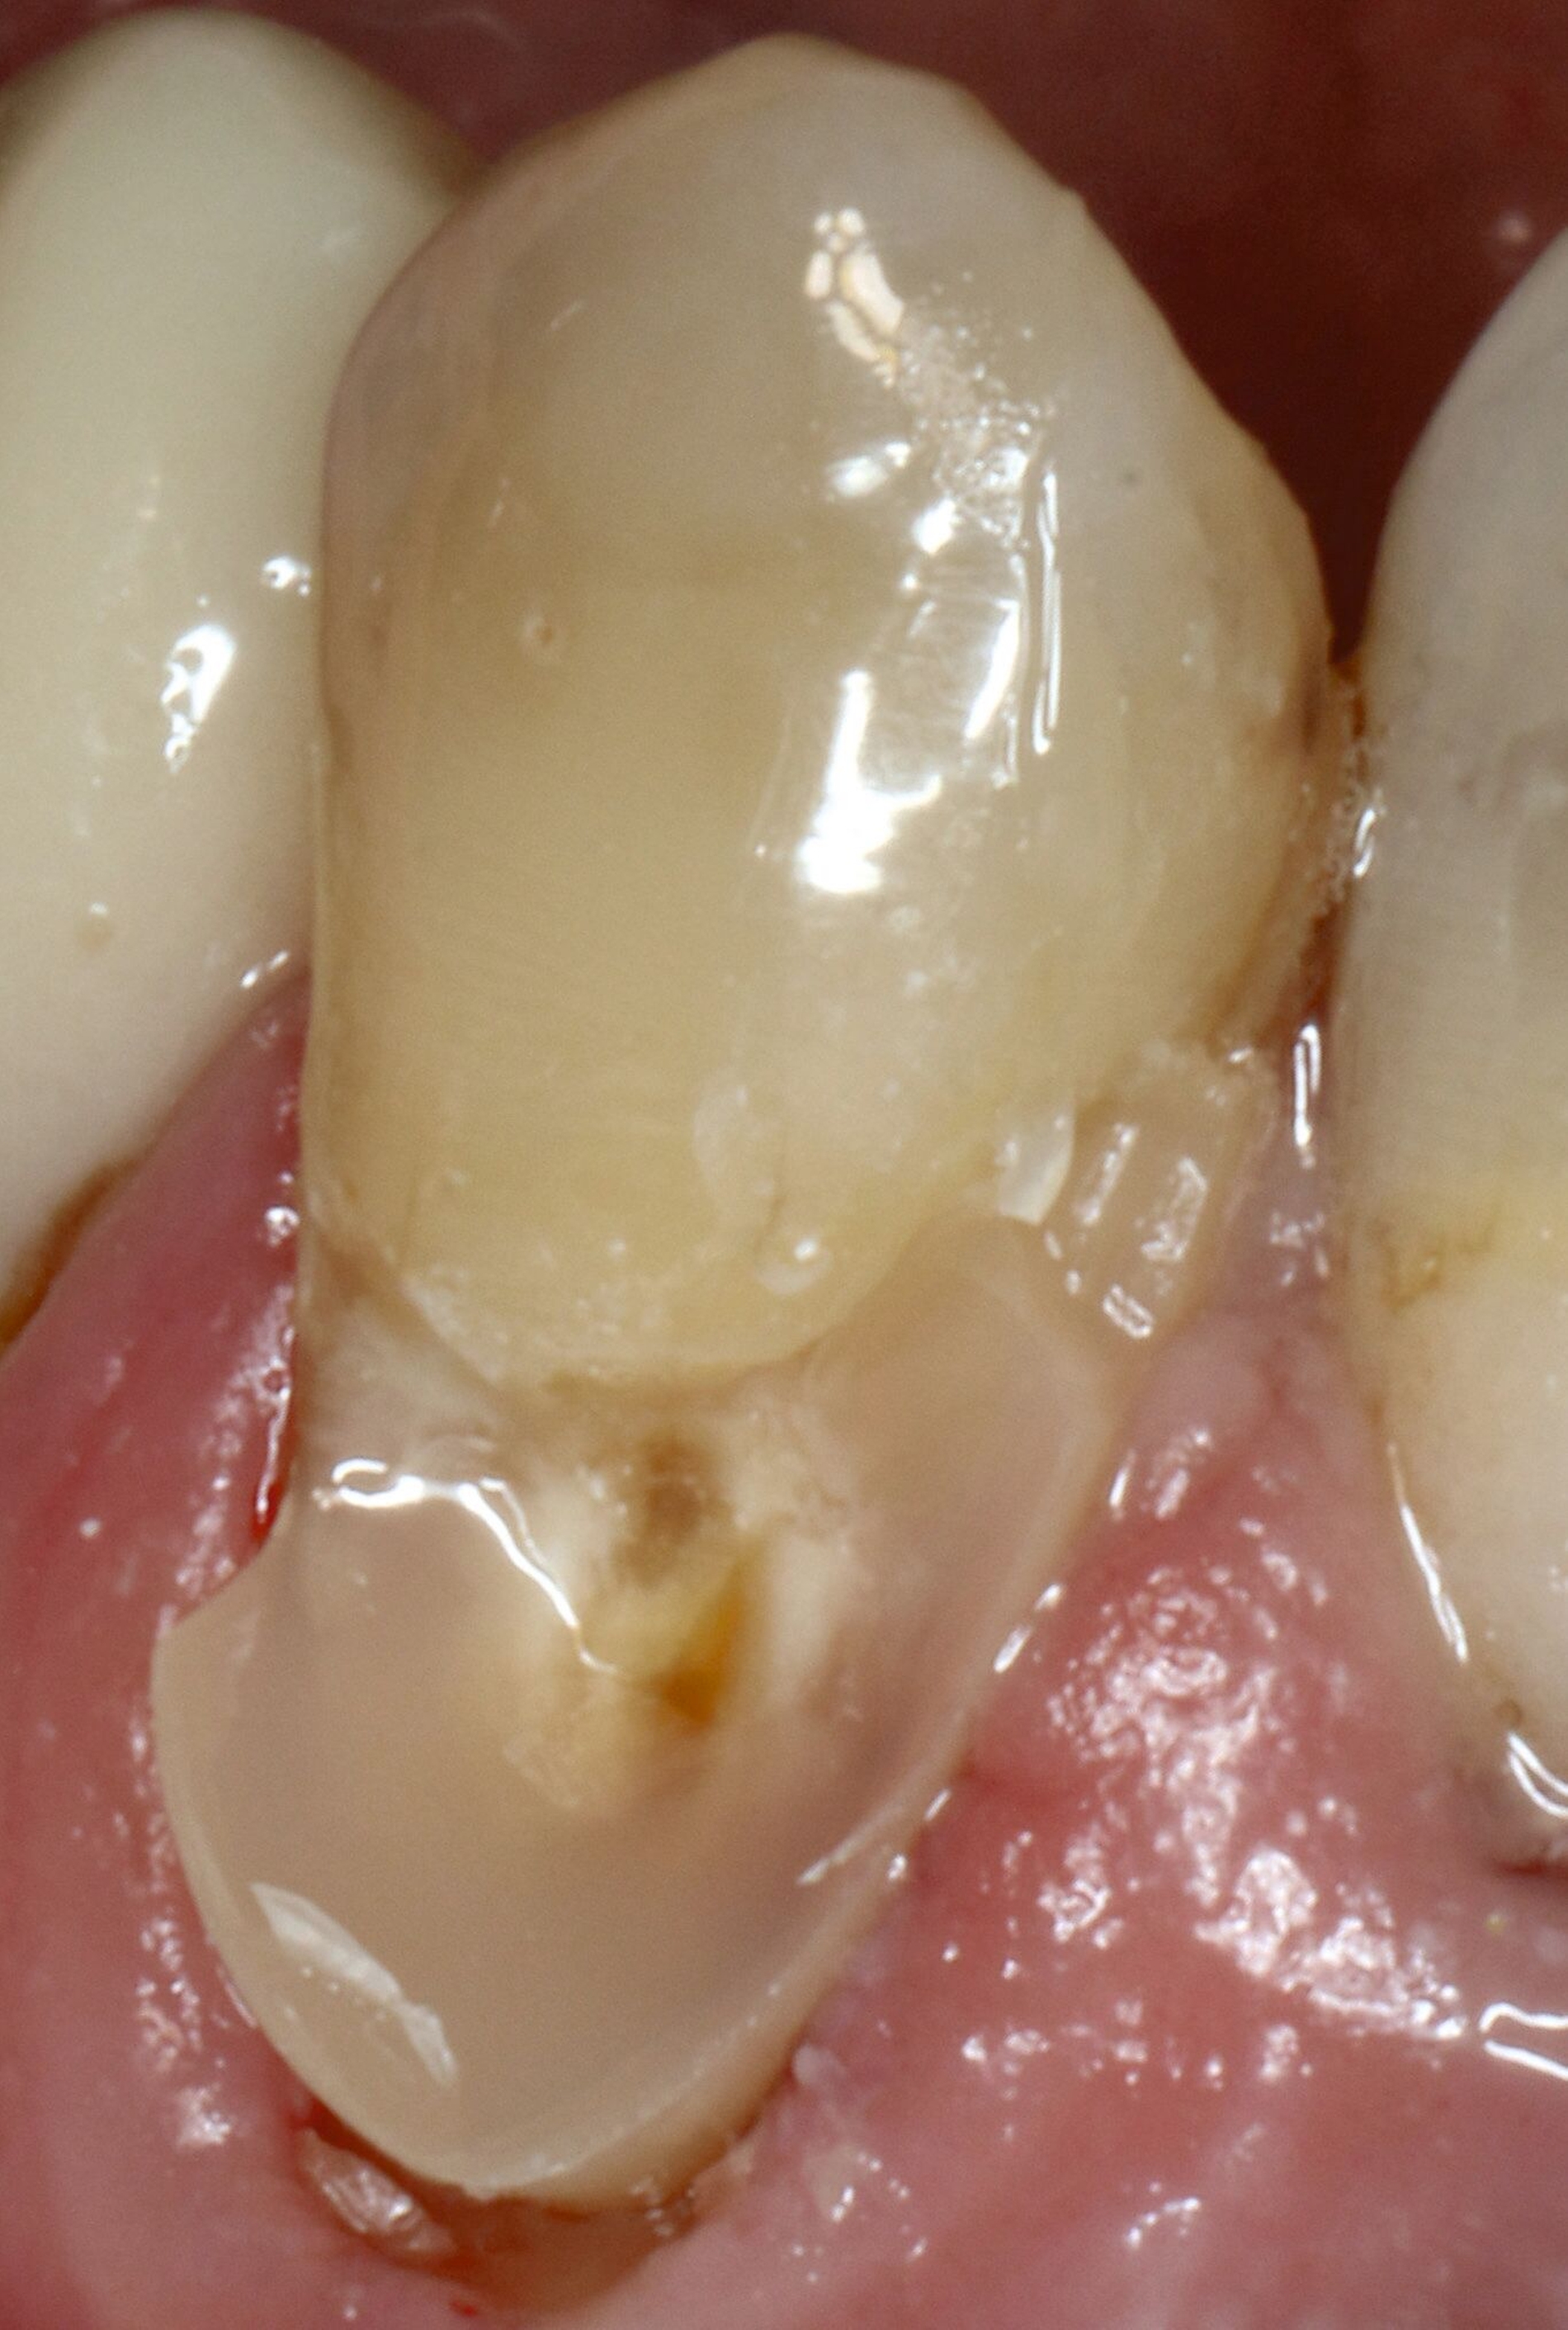

Abbildung 8 beschreibt einen Behandlungsablauf bei einer präexistenten Restauration an Zahn 23 mit deutlich sichtbarer Sekundärkaries zervikal und approximal (Abbildung 8a). Nach der Entfernung der alten Restauration (acht Jahre) zeigt sich das ganze schwer zu restaurierende Ausmaß des Defekts (Abbildung 8b).

In solchen Fällen mit kaum zu kontrollierenden subgingivalen Rändern greifen wir vermehrt auf Stahlmatrizen zurück, die zervikal selbst bei extremen Fällen wie hier noch stabil nach subgingival geschoben werden können, die meist aber mit dem Finger fixiert werden müssen (Abbildung 8e). Bei dieser Technik ist es hilfreich, zunächst den subgingivalen Anteil mit einem gut fließenden Flowable zu füllen (Abbildung 8f), dann die Matrize abzunehmen, nachzufinieren, das Komposit sandzustrahlen und den breit angeschrägten Schmelz mit Phosphorsäure zu ätzen.

Dann wird der gesamte Bondingprozess wiederholt. Die erste Schicht zervikal steht zunächst nach labial über, dieser Kragen kann aber leicht mit einer Finierflamme wieder reduziert werden. Als Schichttechnik bietet sich im weiter koronalen Anteil an, die Fläche mit Flow zur besseren Benetzung auszukleiden, danach den Kern der Restauration aus modellierbarem Komposit zu gestalten und die oberste Schicht wieder aus Universal-Flow zu modellieren, weil dadurch eine blasenfreie Oberfläche erzielt werden kann (Abbildungen 8g und 8h).